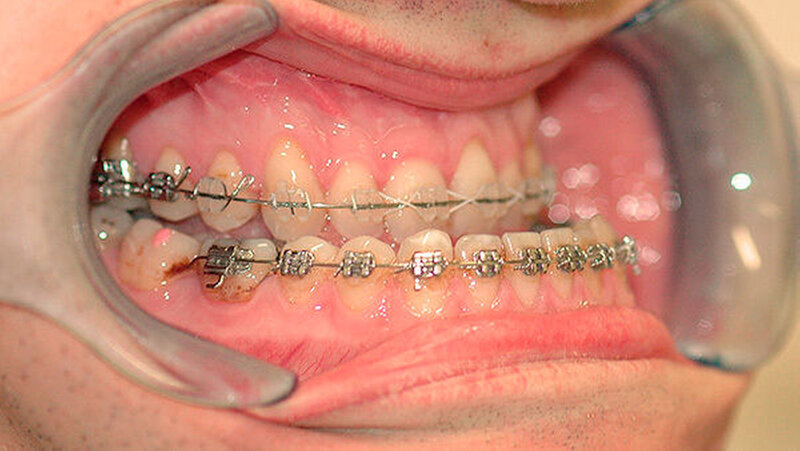

Das deutlich harmonischeres Profil drei Monate nach der Operation: Im Mai des nachfolgenden Jahres wurden die Metallplatten in einem ambulanten Eingriff wieder entfernt. Eine Multibandapparatur hält die Zähne noch "in der Reihe". Der Patient kann heute dank der individuellen innovativen Behandlung ein normales Leben führen, die Gesichtsästhetik und seine Kaufunktion sind vollständig wiederhergestellt.